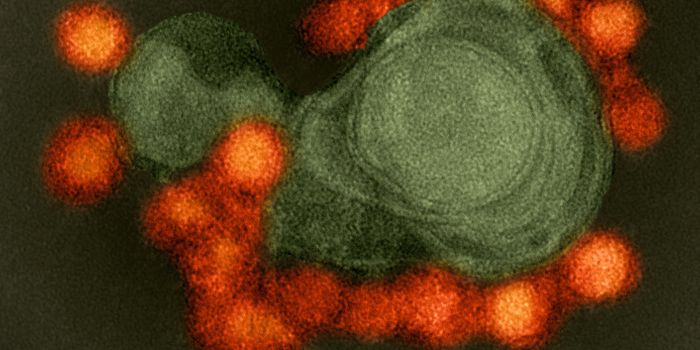

APR 04, 2022Cell & Molecular BiologyAbout 1.5 million new HIV infections are thought to have occurred last year, and while COVID-19 has dominated concerns a ...